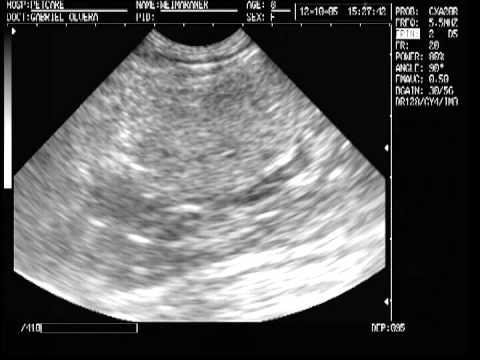

Somos el hospital Veterinario más grande de Querétaro con la tecnología más moderna en diagnóstico médico.